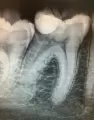

Здравствуйте, примерно 7-8 месяцев назад мне поставили пломбу на 6 верхний зуб. Недавно начала замечать, что зуб под пломбой чернеет. Может быть, что часть зуба будут удалять, или вообще весь зуб?

Добрый день, очень странный вопрос уважаемая София. Как можно по переписке решить, необходимо удалять зуб или нет? Если зуб черный, то совершенно не обязательно его удалять. Рекомендую обратиться к нам на очный прием и при тщательном анализе можно диагностировать состояние зуба и принять решение о возможных планах лечении. Всего вам доброго!